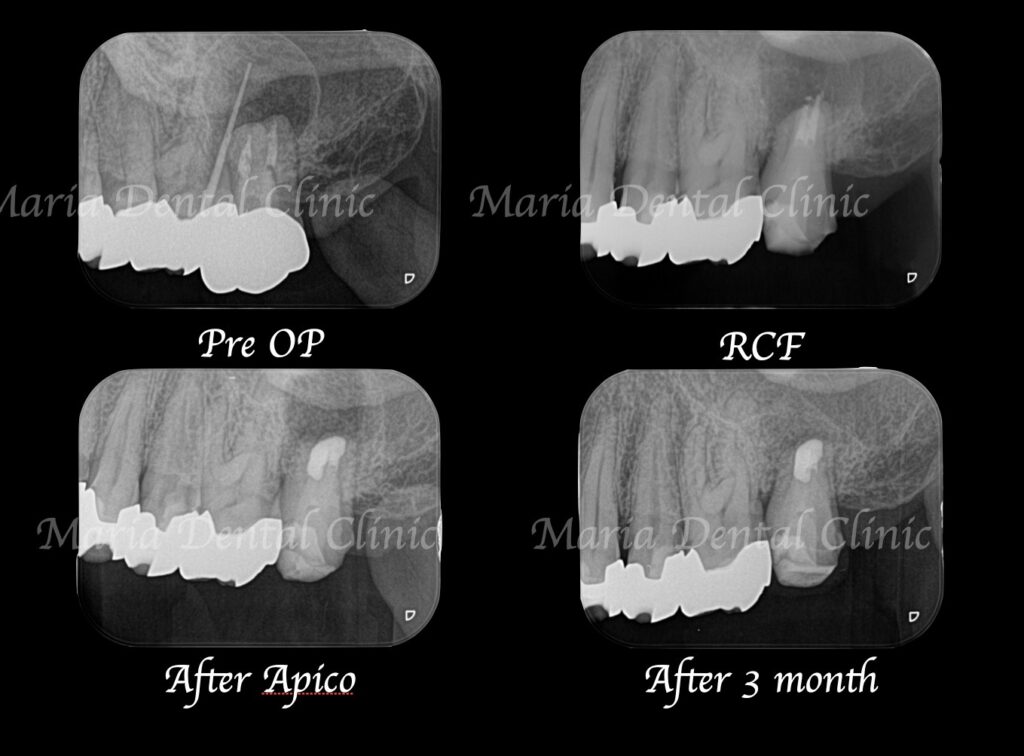

当院で精密根管治療を施しましたが、瘻孔(フィステル・サイナストラクト)を消失させることが難しく、追加処置として歯根端切除術(今回は意図的再植術)を行いました。また、術前に撮影したCT画像より、根尖性歯周炎が原因と考えられる上顎洞炎(蓄膿症/ちくのうしょう)の併発も確認できました。

歯根端切除術(意図的再植術)から3週間後の経過観察で、瘻孔の消失が確認できました。また、術後3ヶ月経つと、根尖部付近に確認できていた根尖性歯周炎も小さくなりました。患者様も「噛んだときにも、違和感や痛みなどはない」ということで、予後は良好だと判断しました。今後は最終補綴処置を行う予定です。

根尖性歯周炎の主な原因が細菌感染であることは、当院のこれまでの症例やコラムを読んでいただければ、お分かりかと思います。そのため、根尖性歯周炎の病変の大きさは、治癒に至る(病変が消失する)までの時間に影響を及ぼします。しかし、歯内療法専門の歯科医師による治療レベルで処置を行った場合は、病変の大きさはほぼ影響しません。

今回の症例の患者様は、病変が大きいことから、かかりつけ医に抜歯を宣告されて、当院へ相談に来られました。当院の治療により、瘻孔(フィステル)は消失し、歯根端切除術(意図的再植術)3ヶ月後の経過観察では、明らかな病変の縮小が確認されました。